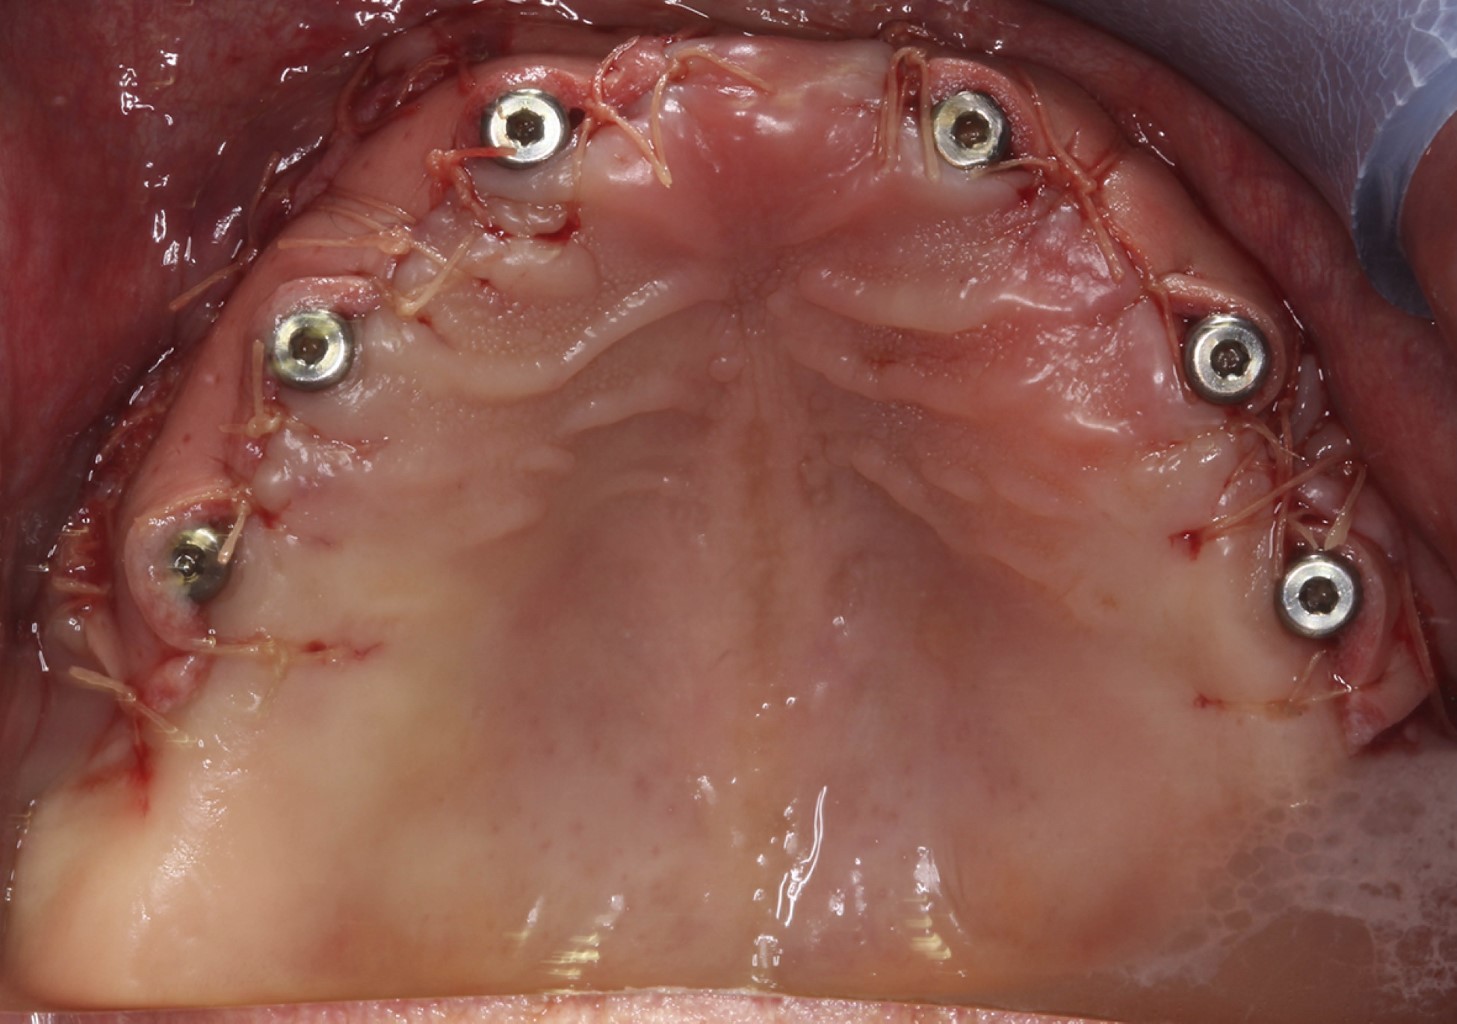

A la exploración clínica intraoral se observó la presencia de seis implantes en el maxilar con ausencia total de mucosa queratinizada y tejido insertado, fenotipo delgado menor a 0.5 mm, se observaban las cuerdas del implante del incisivo lateral izquierdo a través de la mucosa, así como la presencia de un surco periimplantario (Figura 1).

Figura 1